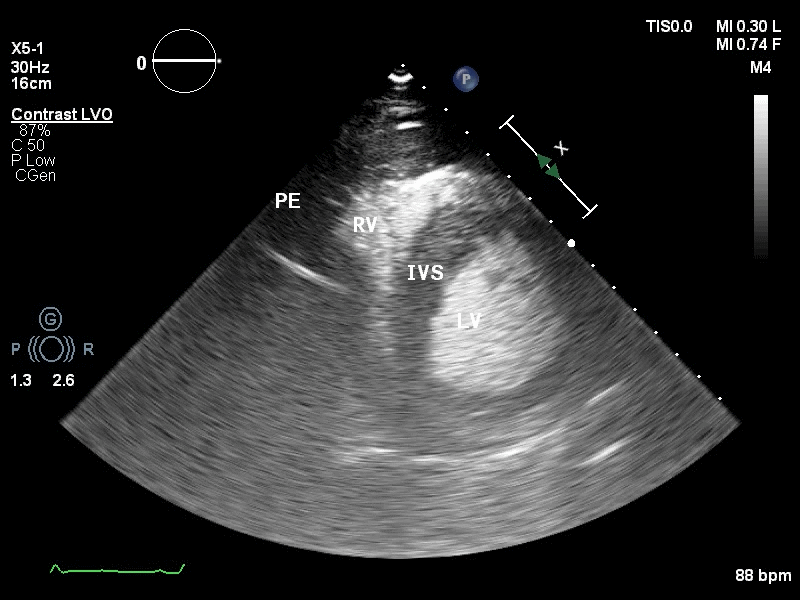

(图3)

(图4)

图3和图4: 彩色多普勒:心包腔可见可疑的较明亮彩色信号。

为进一步明确诊断,行床旁心脏超声造影,可见Contrast-LVO模式下,可见心包腔内可见由左室心尖缓慢飘出的点状造影剂声像。